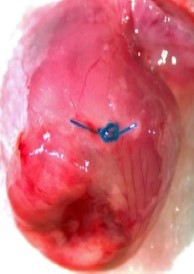

LAD Reperfusion Model: 30 Minute Ischemia with 2 Hour Reperfusion

Pictured: Cardiac Perfusion With Evans Blue Dye To Define Infarct zone.